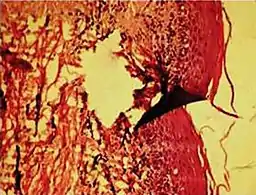

In electron microscopy, distortions may be produced in the drying out of the specimen. Staining can cause the appearance of solid chemical deposits that may be seen as structures inside the cell. Different techniques including freeze-fracturing and cell fractionation may be used to overcome the problems of artifacts.[1]